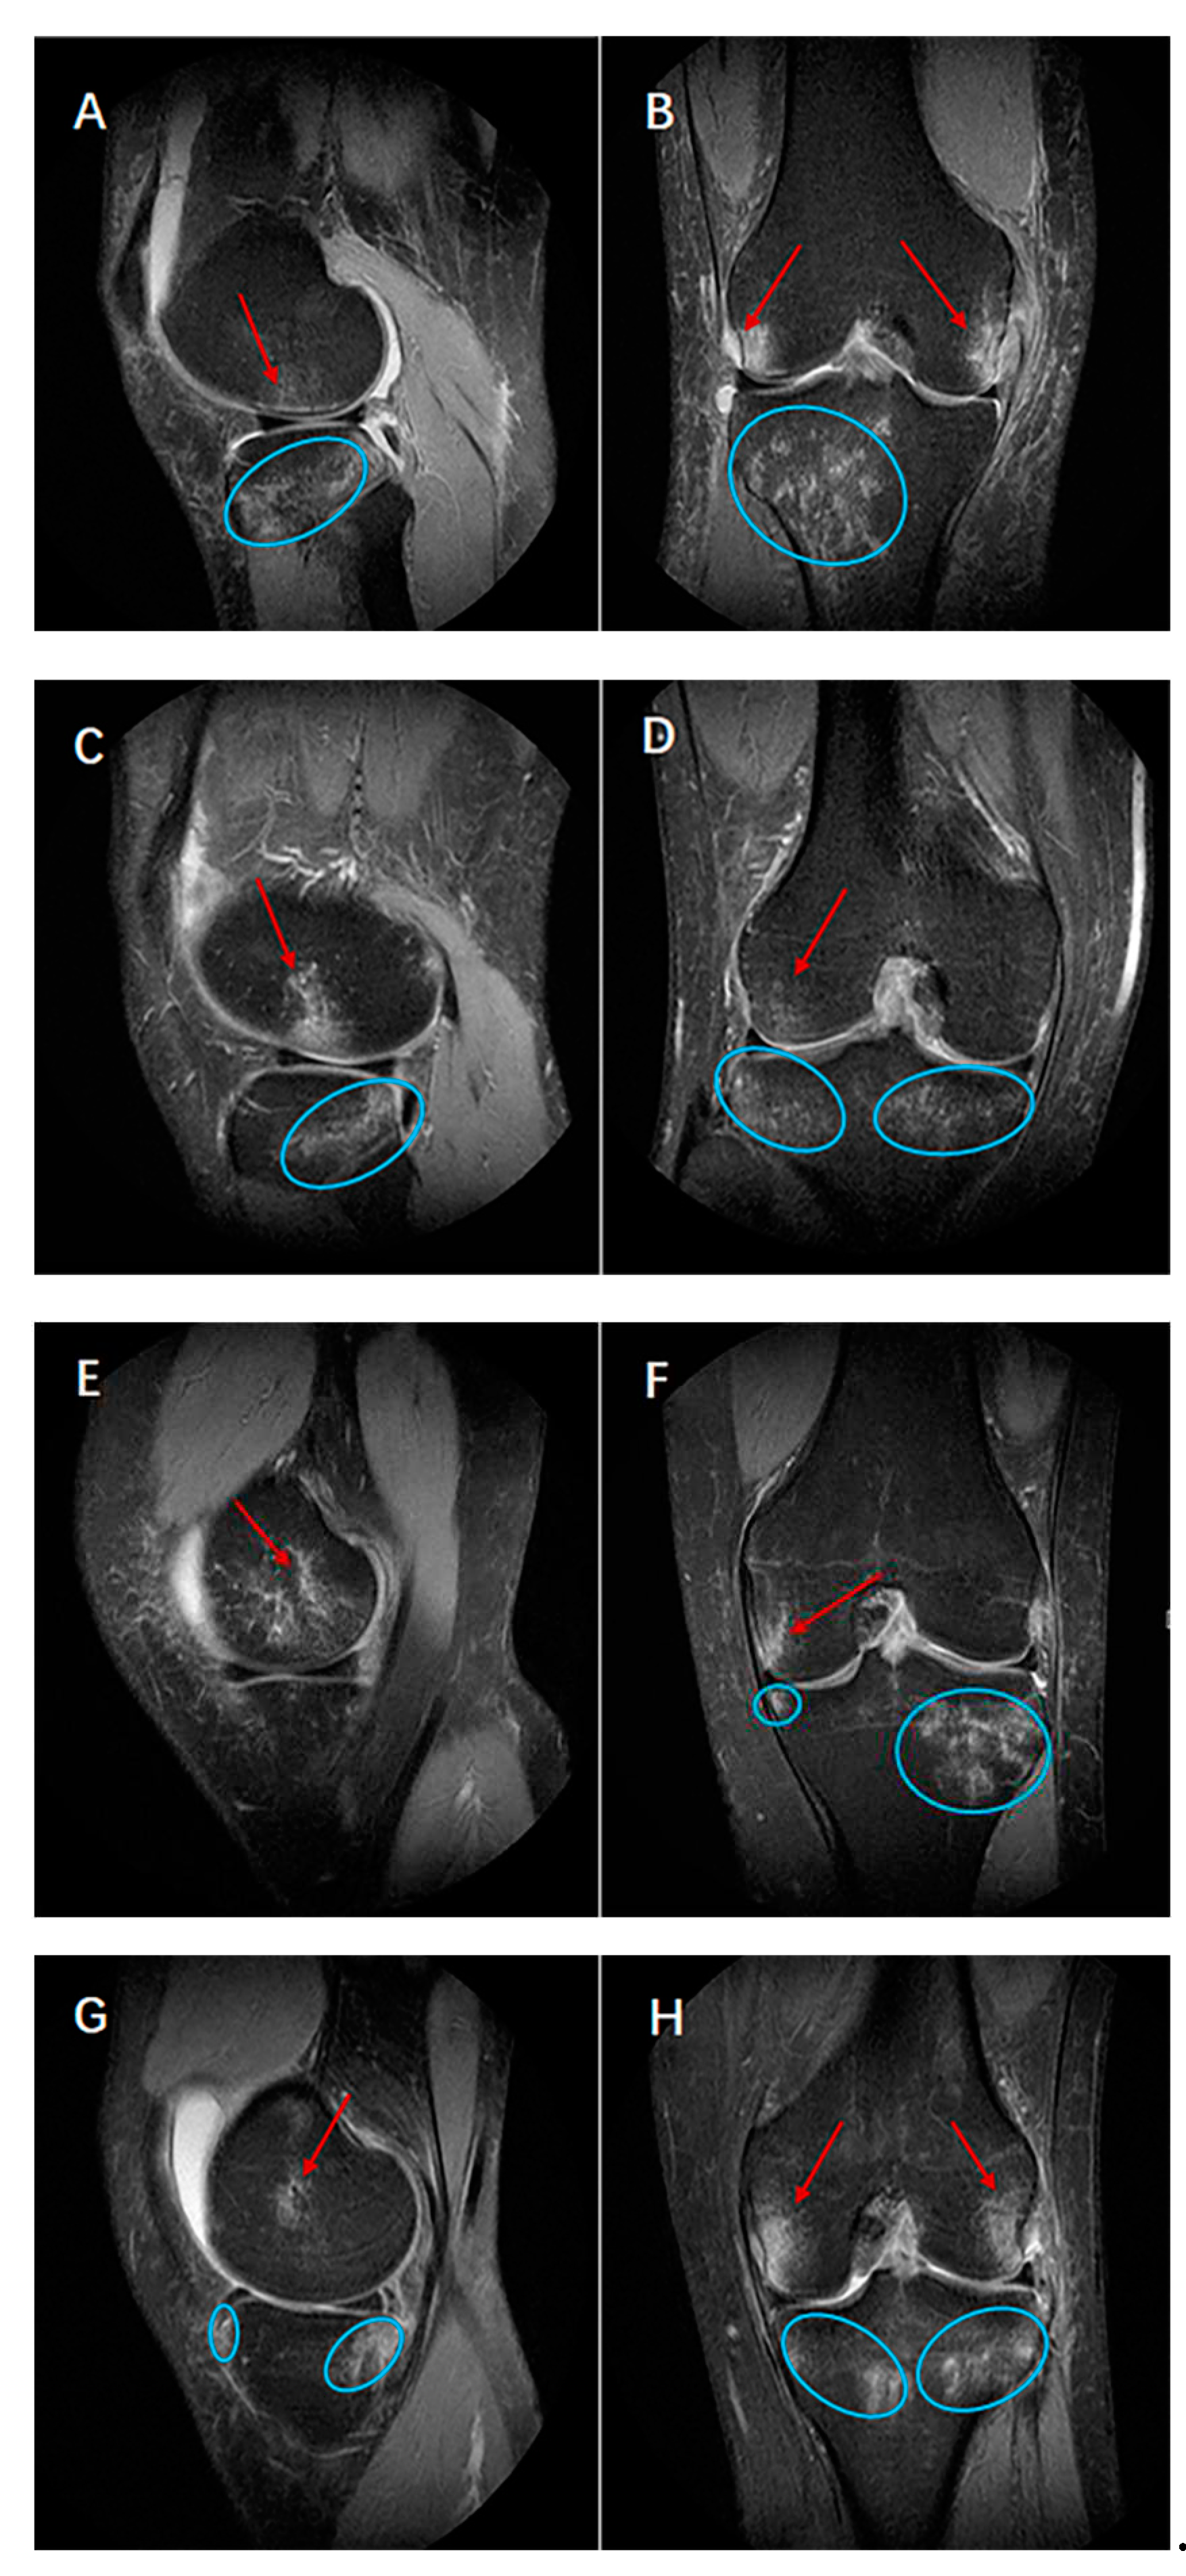

By calculating the position of bone bruises in sagittal and coronal planes, there were 4 kinds of bone bruise (1-,2-,3-,4- bone bruises) patterns among ACL rupture bone bruise patients (Table 2). The most common two patterns of ACL rupture were 3 (40%) bone bruises (lateral side of femur and both lateral and medial side of tibia, LF+BT [23%]; both lateral and medial side of femur and lateral side of tibia, BF+LT [16%], medial side of femur and both lateral and medial side of tibia, MF+BT [1%]), followed by 4 (29%) bone bruises (both lateral and medial side of femur and tibia, BF+BT) (Figure 3, A-H) and 2 (30%) bone bruises (lateral side of femur and tibia, LF+LT [19%]; medial side of femur and lateral side of tibia, MF+LT [5%];lateral side of femur and medial side of tibia, LF+MT [4%]; medial side of femur and tibia, MF+MT [1%]; lateral and medial side of tibia, 0+BT [1%]). Only 1 bone bruise including lateral side of tibia (0+LT, 1%).

AB, lateral side of femur and both lateral and medial side of tibia (LF+BT); CD, both lateral and medial side of femur and lateral side of tibia (BF+LT); EF, medial side of femur and both lateral and medial side of tibia (MF+BT); GH, both lateral and medial side of femur and tibia (BF+BT).

Figure 3. The most common 3 bone bruises and 4 bone bruises patterns of ACL rupture. ACEG, sagittal plane; BDFH, coronal plane. Red arrow, femoral bone bruise. Blue ellipse, tibia bone bruise.

To test our hypotheses, we reviewed the MR images ACL rupture and patellar dislocation patients with bone bruises. Imaging sequences of the sagittal and transverse planes were used to quantitatively calculated relative lateral-medial and superior-inferior direct positions of bone bruises in distal femur, proximal tibia and patella. As showed in our study, there were 4 (1-,2-,3-,4-) kinds of bone bruise patterns of ACL rupture, and the commonly seen bone bruise patterns were 3- (LF+BT, BF+LT, MF+BT) , followed by 4 (BF+BT) and 2- (LF+LT, MF+LT, LF+MT, MF+MT, 0+BT; Table 2) bone bruises in femur and tibial respectively while there was only 1 pattern of patellar dislocation which in lateral femur and medial patella (Figure 1 and Figure 2, Table 3). ACL rupture and patellar dislocation have the completely different bone bruise patterns which may represents the different injury mechanisms of the knee. The ACL rupture patients who displayed 1- bone bruises of femur and tibia respectively, suggesting that the knee displayed anterior and translated tibia to the femur at the time of injury. The ACL rupture patients who displayed 3- or 4- bone bruises in 1- or 2- femur and 2- tibia suggesting that the knee joint was unstable when ACL was injured, not only anterior and translated tibia to the femur but also shaking obviously in the lateral-medial direction was performed of the knee at the time of injury. Similarly, the difference of the superior-inferior direct positions of femoral and patellar bone bruises in patellar dislocation also indicated that different bone bruise patterns reflect different knee flexion angles at the time of injury (Figure 4 and Figure 5).